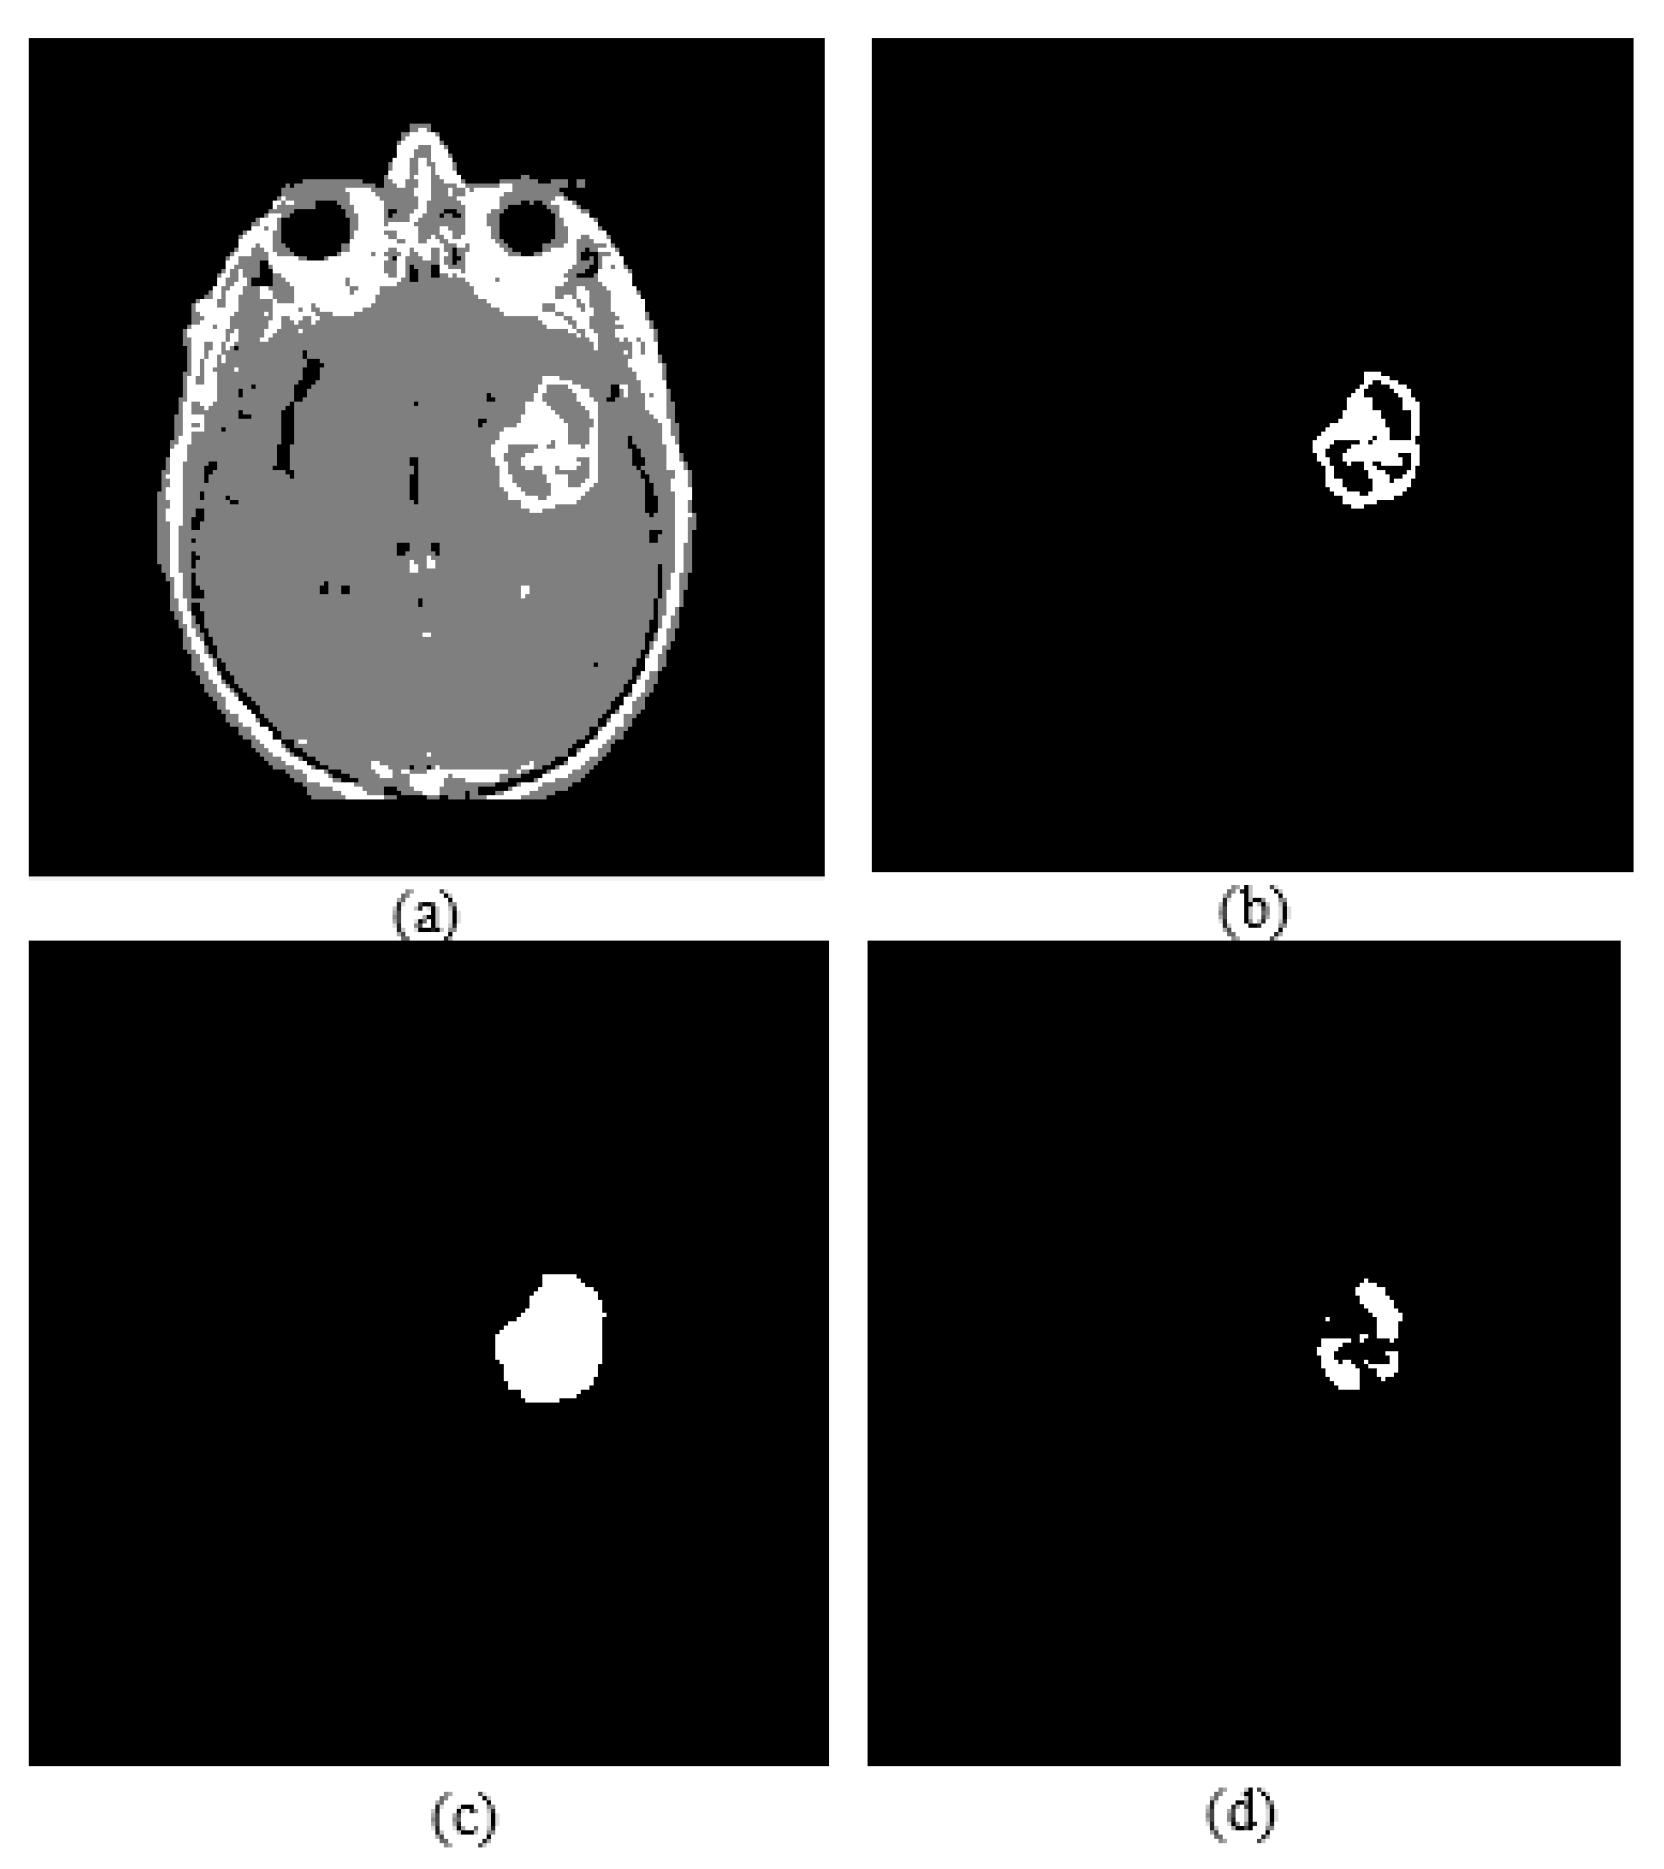

Active core segmentation and the volume estimation stage involve masking and FCM clustering operations, as outlined in Figure 11. The T1C image is converted to a binary image via FCM and a morphological opening operation (Figure 12c), and then skull stripping and whole tumor masks (Figure 12d,e) are applied on this image to obtain the enhancing/active core (Figure 12f). To obtain the necrotic/cystic core, a morphological closing operation is applied on the active core region (Figure 13c), then the active core is subtracted from this image (Figure 13d).

Figure 12.

(a) T1C image; (b) fuzzy c-means clustering result; (c) binary image including active core; (d) skull stripping mask; (e) whole tumor mask; (f) enhancing tumor.